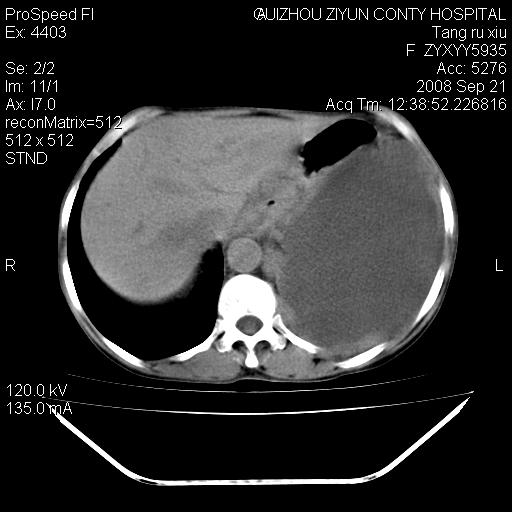

f、57岁,上腹痛.2月,近来胸闷。2月前在外院摄胸片示左侧胸腔少量积液。

(患者腹痛入院,欲吐,临床医生说禁饮,所以没有口服对比剂)

考虑----左侧胸腹腔积液----压迫性肺不张----心包积液---肝脏多发低密度影-----穿刺抽液后复查

左侧胸壁见一结节影,肝脏多发低密度影,左侧胸腔大量积液。建议增强

肝脏大小形态尚可,其实质内可见多发大小不等的低密度影,边缘模糊。肝门区结构紊乱,腔静脉腹主动脉旁可见多发软组织密度影,部分融合成团块状,并向下延伸。胰腺及十二指肠结构显示不清。腹腔内脐后肠管走形僵硬,管壁可见增厚。盆腔内可见多个淋巴结影。所扫层面左侧胸腔可见大量弧形水样密度影,其内侧可见被压缩的肺组织影。左侧胸壁可见一小结节样软组织密度影,边缘模糊。心脏纵隔向右侧移位。心脏包膜内可见囊样低密度影,其内侧心房室周围可见一圈气体样密度影。纵隔内大血管旁可见多发软组织团块影,部分融合。

1.腹膜后淋巴瘤侵及肝脏,肺内及纵隔内多发转移。2.左侧大量胸腔积液并压缩性肺不张。3.心包脓肿可能,转移不除外。4.脐后局部肠管管壁增厚,考虑炎症可能,肿瘤不除外。